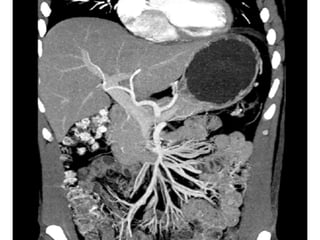

Blood Supply

Celiac trunk - 3 branches – to liver,

gallbladder, esophagus, stomach,

duodenum, pancreas, and spleen

Superior mesenteric– to pancreas and

duodenum, small intestine and part of

colon

Inferior mesenteric– to colon